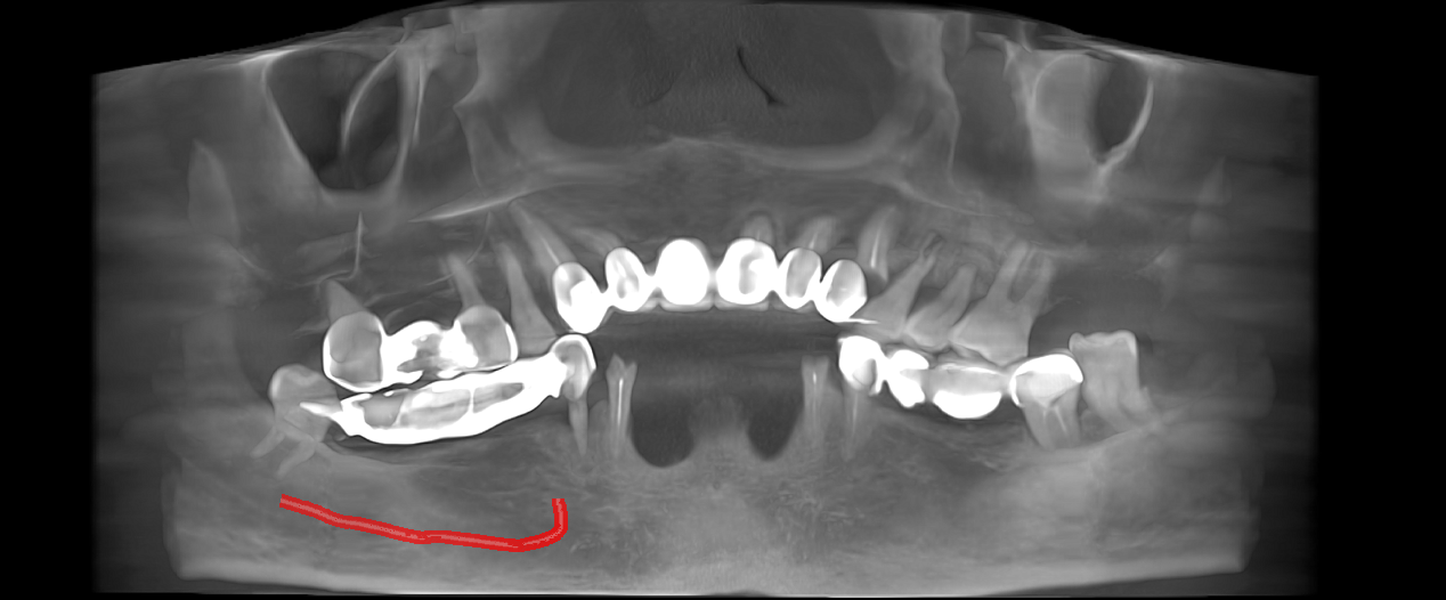

Tomografie (CBCT)

Caz 1